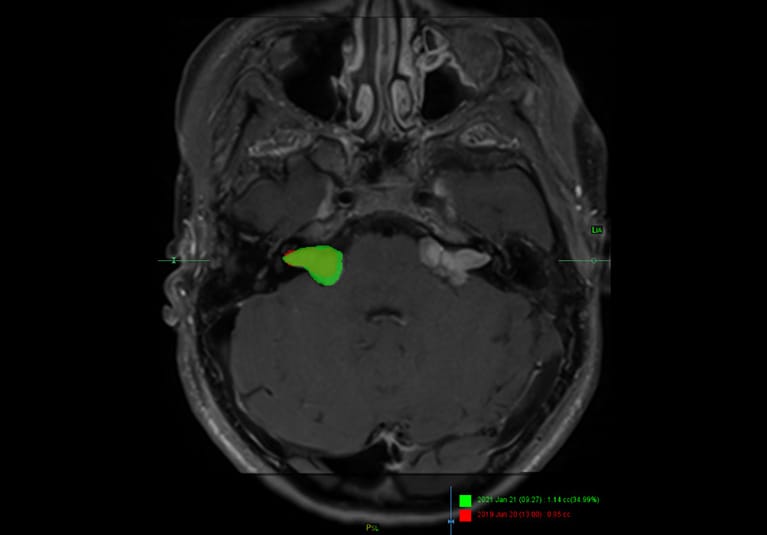

Overlays of MRI demonstrate the growth of bilateral vestibular schwannomas over an 18-month period in a patient with neurofibromatosis type 2. The current tumor volume is shown in green, and the earlier tumor volume in red.

The specialists also evaluate overlays of a patient's current scans and scans taken two years earlier. "We can drop the previous image right on top of the current image, and then use a slide bar to pan between them," Dr. Lane says. "Often that analysis can be even more sensitive than volumetric changes in assessing tumor growth."

Volumetric measurements of tumors — obtained by segmenting and analyzing patients' MRIs in a 3D laboratory — are assessed. "What might not be readily evident by visual examination of the MRI can be detected with volumetric analysis," says John (Jack) I. Lane, M.D., a neuroradiologist at the Rochester campus of Mayo Clinic.

Unlike most tumors, which are generally spherical or elliptical, NF2 tumors have highly irregular shapes. "As a result, a 2- or 3-millimeter change on a linear scan can result in a 50% to 80% change in total tumor size, which would be an indication that treatment is needed," says Michael J. Link, M.D., a neurosurgeon at Mayo's campus in Rochester, Minnesota.